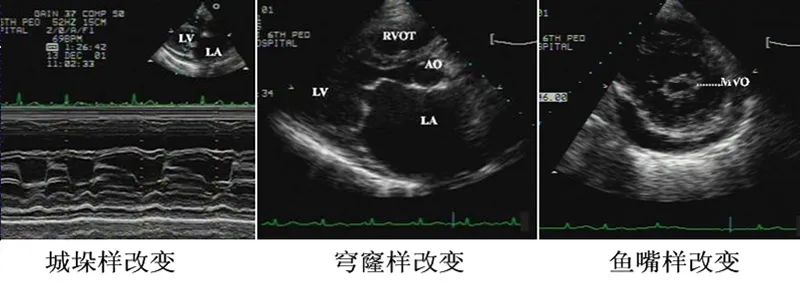

左房扩大,二尖瓣前叶呈“城垛样”改变,射血分数斜率下降,二尖瓣开放幅度降低,前后叶同向运动。瓣叶增厚,回声增强。

舒张期在胸骨旁左室长轴切面可见舒张期二尖瓣开放受限,开放时呈“穹窿样”或“僧帽样”瓣膜回声增强,瓣膜间距小于2 cm;左室短轴二尖瓣水平切面见“鱼嘴状”瓣口,表示交界处粘连,瓣口面积缩小。左房附壁血栓是二尖瓣狭窄的常见并发症。

图1. 二尖瓣狭窄M超和二维超声形态改变。